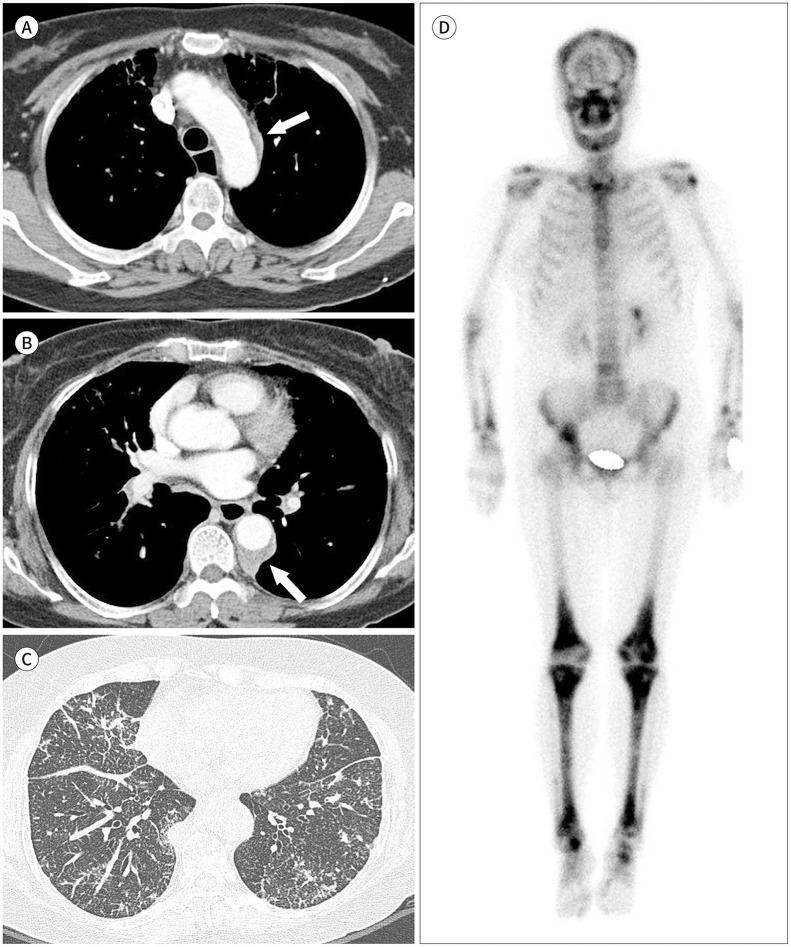

Immunoglobulin G4-related disease (IgG4-RD) is a chronic inflammatory condition involving multiple organs, including the salivary or lacrimal glands, orbit, pancreas, bile duct, liver, kidney, retroperitoneum, aorta, lung, and lymph nodes. It is histologically characterized by tissue infiltration with lymphocytes and IgG4-secreting plasma cells, storiform fibrosis, and obliterative phlebitis. In the thoracic involvement of IgG4-RD, mediastinal lymphadenopathy and perilymphangitic interstitial thickening of the lung are the most common findings. Peribronchovascular and septal thickening and paravertebral band-like soft tissue are characteristic findings of IgG4-RD. Other findings include pulmonary nodules or masses, ground-glass opacity, alveolar interstitial thickening, pleural effusion or thickening, mass in the chest wall or mediastinum, and arteritis involving the aorta and coronary artery. Radiologic differential diagnosis of various malignancies, infections, and inflammatory conditions is needed. In this review, we describe the imaging findings of IgG4-RD and the radiologic differential diagnoses in the thorax.

免疫球蛋白G4相关性疾病(IgG4-RD)是一种累及多个器官的慢性炎症性疾病,这些器官包括唾液腺或泪腺、眼眶、胰腺、胆管、肝脏、肾脏、腹膜后、主动脉、肺和淋巴结。其组织学特征为淋巴细胞和分泌IgG4的浆细胞浸润组织、席纹状纤维化和闭塞性静脉炎。在IgG4-RD累及胸部时,纵隔淋巴结肿大和肺淋巴管周围间质增厚是最常见的表现。支气管血管周围和小叶间隔增厚以及椎旁带状软组织是IgG4-RD的特征性表现。其他表现包括肺结节或肿块、磨玻璃影、肺泡间质增厚、胸腔积液或增厚、胸壁或纵隔肿块以及累及主动脉和冠状动脉的动脉炎。需要对各种恶性肿瘤、感染和炎症性疾病进行影像学鉴别诊断。在本综述中,我们描述了IgG4-RD的影像学表现以及胸部的影像学鉴别诊断。